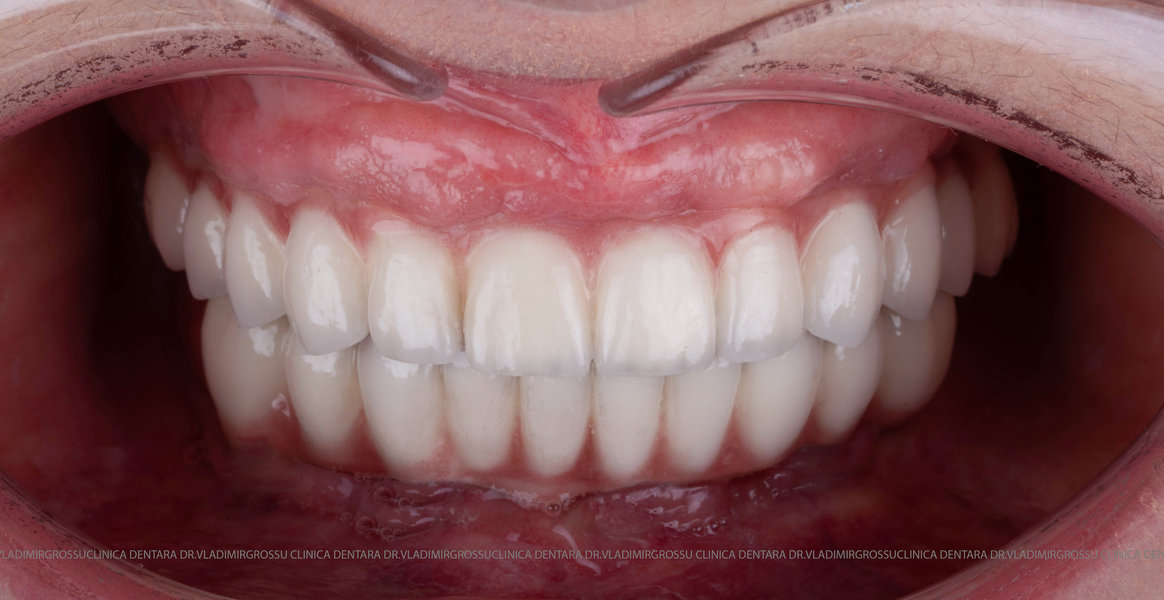

Această metodă este recomandată pacienților edentați total sau celor cu lipsuri dentare multiple. Procedura se realizează într-o singură etapă, iar pacientul primește proteza provizorie în ziua următoare intervenției. De regulă, proteza provizorie este realizată din masă plastică frezată. Suturile se îndepărtează după 5-7 zile.

La aproximativ 6 luni de la prima etapă, pacientul revine pentru protezarea definitivă. În această fază, medicul lucrează la nivelul multiunit-urilor și nu direct pe implanturi, ceea ce reduce riscurile pentru implant în etapa protetică.

Pentru pacienții cu edentație extinsă sau dinți nefuncționali, conceptele All-on-4 și All-on-6 oferă soluții fixe, moderne și eficiente, care asigură estetică, confort și funcționalitate superioară față de proteza mobilă.